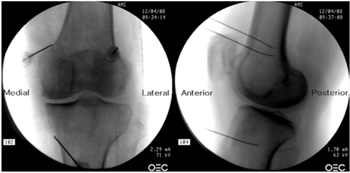

Figura 2